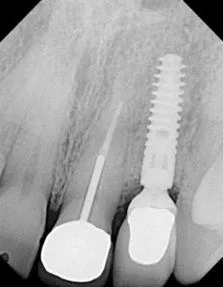

Implant placement with using Sinus Bone Graft

Before

After